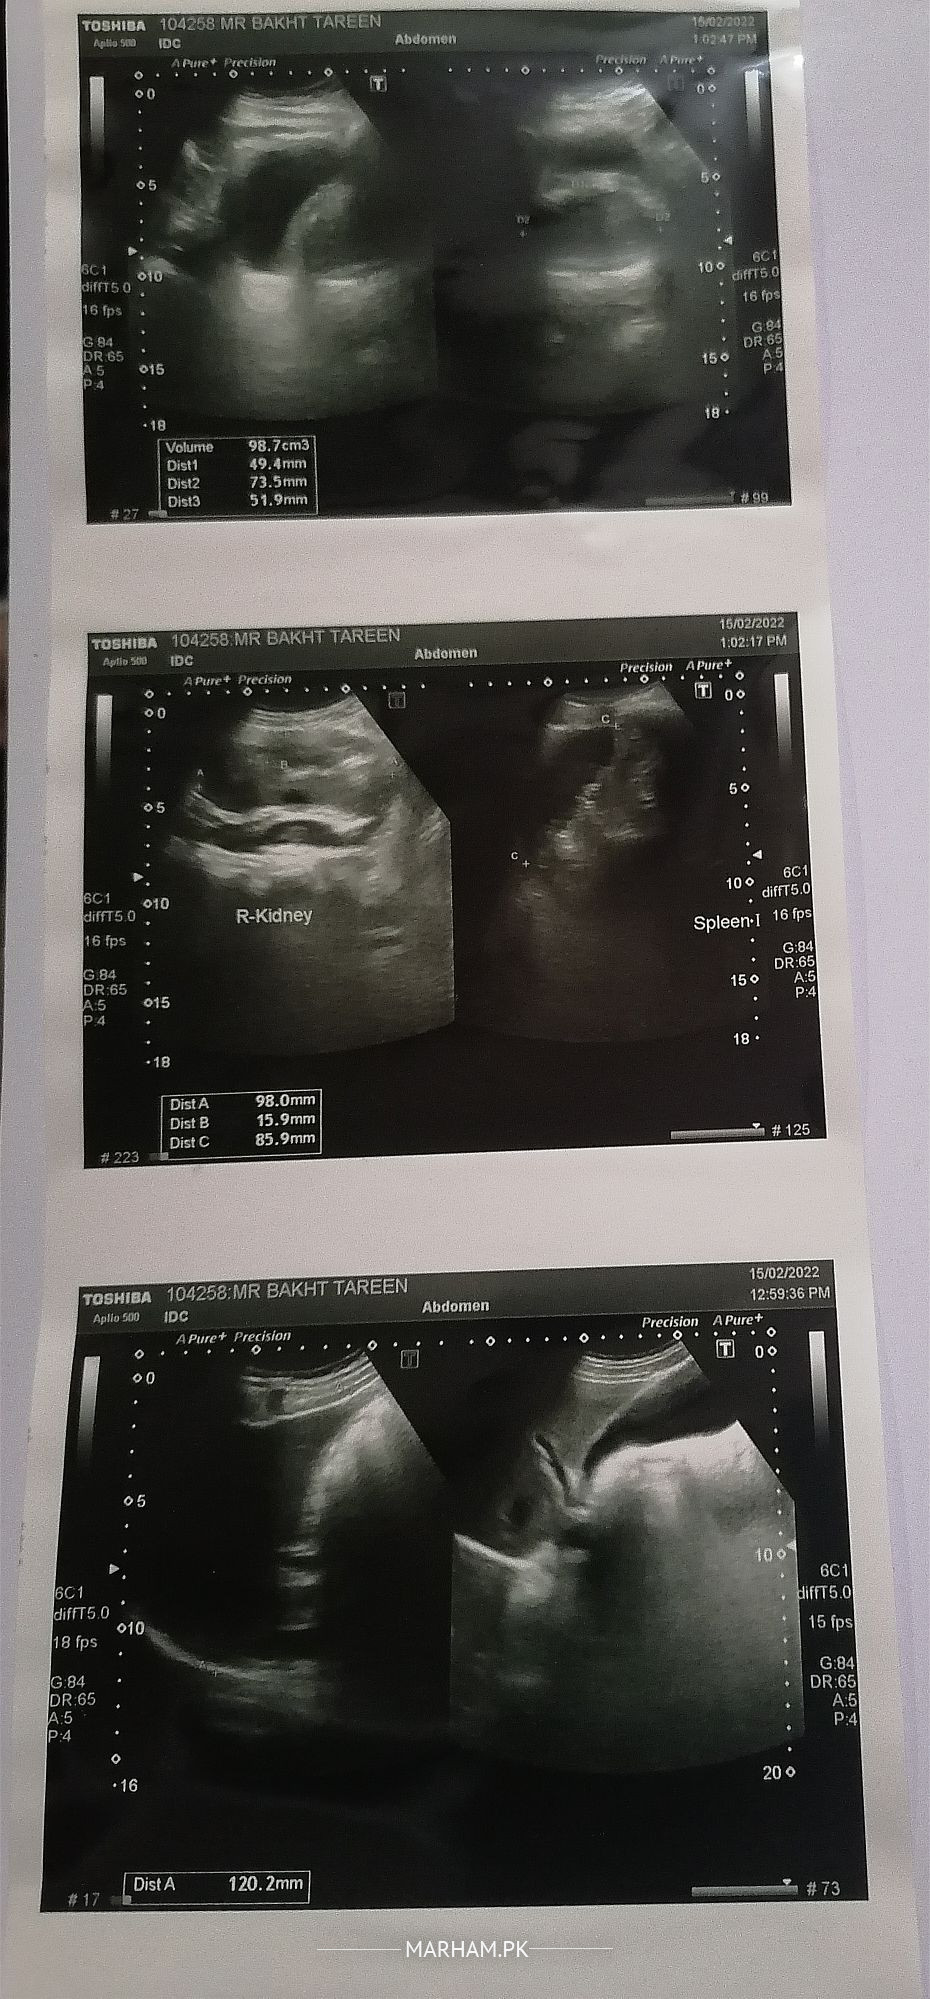

We've Abd U/S yesterday and it shows 98mm. The Doctor said that you need to take appointment with urologist for operation.

The Abd U/S is attached along with report and tests data.